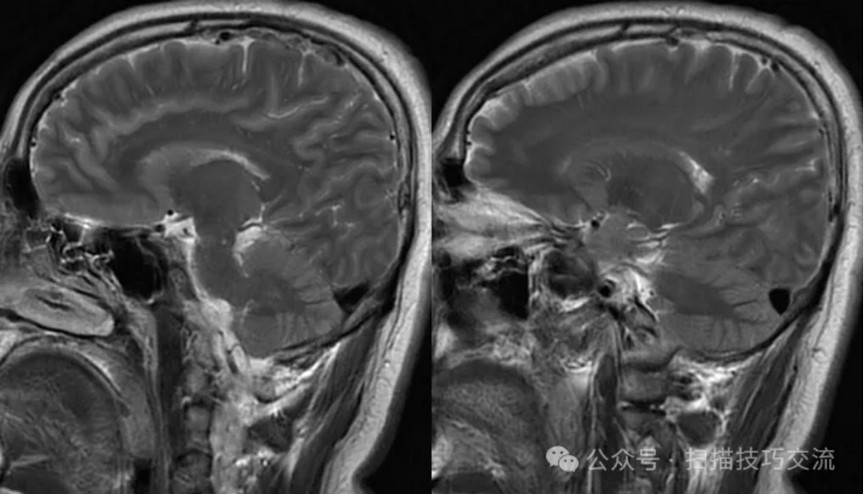

临床申请:颅脑平扫,静脉成像,磁敏感成像,颅内静脉血管黑血成像。

颅内静脉黑血成像,CUBE T1fs w/o +c,静脉窦未见异常。